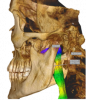

Figure 11. Airway analysis presented on the volume rendering of a large field-of-view CBCT scan.

Figure 11

The applications of CBCT imaging certainly extend beyond endodontic diagnosis. The ultimate goal of imaging is to portray the anatomic "truth" to help in diagnosis and treatment planning. CBCT imaging for the primary evaluation of the airway has been greatly debated. Studies have shown that certain craniofacial patterns are related with smaller dimensions of the upper airway.8 Some of the most common qualitative factors include retrognathia, steep mandibular plane, hypoplastic maxilla, and reduced transverse dimension of the maxilla. Quantitatively, airway volume, minimum cross-sectional area, and airway length can be automatically computed using the imaging software (Figure 11 and Figure 12).9